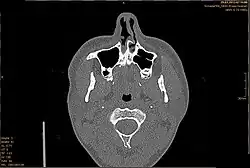

Die Diagnose einer Septumdeviation wird mittels äußerer Inspektion der Nase, vorderer Rhinoskopie, Endoskopie oder Computertomografie (CT) gestellt. Wie stark eine Septumdeviation die Nasenatmung behindert, kann mithilfe einer Rhinomanometrie gemessen werden. Außerdem sollte eine Riechprüfung durchgeführt werden.